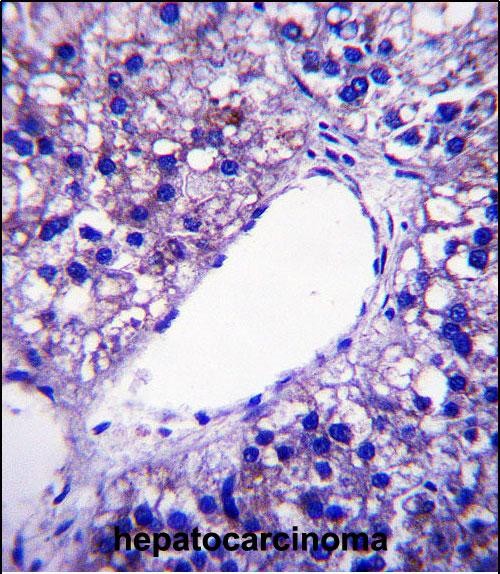

3. **"Immunohistochemical analysis of PNPLA4 expression in human hepatocellular carcinoma"**

- **作者**: Wang X, et al.

- **摘要**: 利用商业化PNPLA4抗体对肝癌组织进行免疫组化分析,发现PNPLA4高表达与肿瘤侵袭性及患者不良预后显著相关,提示其作为潜在生物标志物。